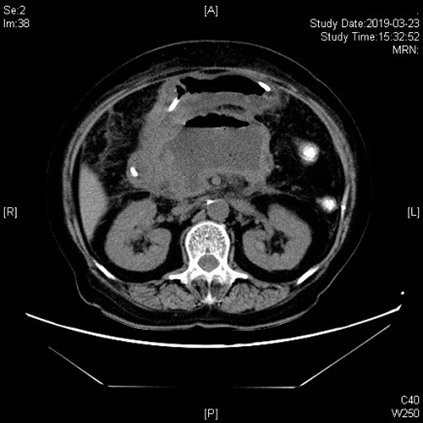

“腹部疼痛已经3个月了,”并且还在逐渐加重影响了她的呼吸。我院东院区内科综合一科的医务人员在完善相关辅助检查后,于3月21日由胡锦华副主任医师为她进行了EUS引导下胰腺假性囊肿穿刺引流术,在胃与假性囊肿之间置入支架,成功将囊液引流至胃内。术后董阿姨的腹痛缓解了,胸闷、憋喘症状也消失了。术后3天复查CT,囊肿已缩小超过50%,效果显著。董阿姨已于近日顺利出院。

术后3天CT